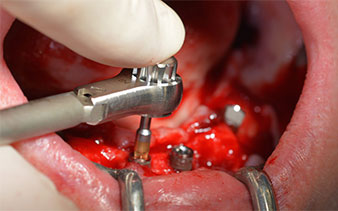

The 64-year-old patient presented with residual dentition of teeth 38, 33 and 43 and a clasp denture in the mandible (Fig. 1 and 2).

The mental foramen was first identified as a limiting anatomical structure and then the cortical bone of the crest was smoothed with the straight handpiece and a large rose-head bur (Fig. 4).